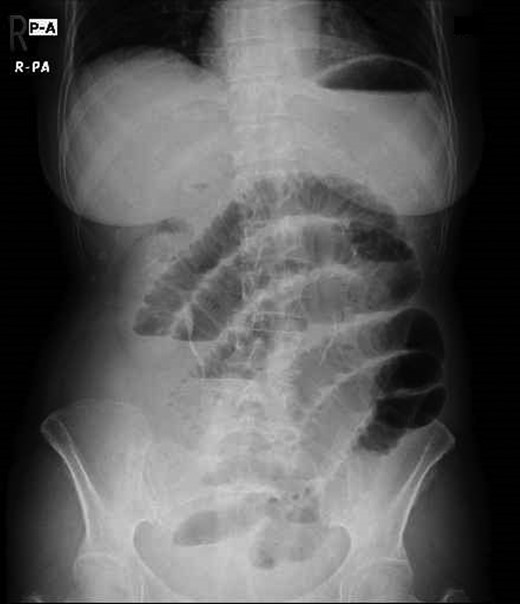

A 73-year-old Japanese woman presented to our emergency department with a 72-hr history of abdominal pain and nausea. Her surgical history included appendectomy and total hysterectomy. Her vital signs on admission were as follows: blood pressure 141/89 mmHg, pulse 76 bpm, temperature 36.9°C. The physical examination revealed lower abdominal tenderness without any peritoneal irritation signs. Laboratory tests included a slightly elevated white blood cells count (9.0 × 103/μl) and C-reactive protein (2.14 mg/dl). Abdominal X-ray showed distended loops of small bowel (Fig. 1).